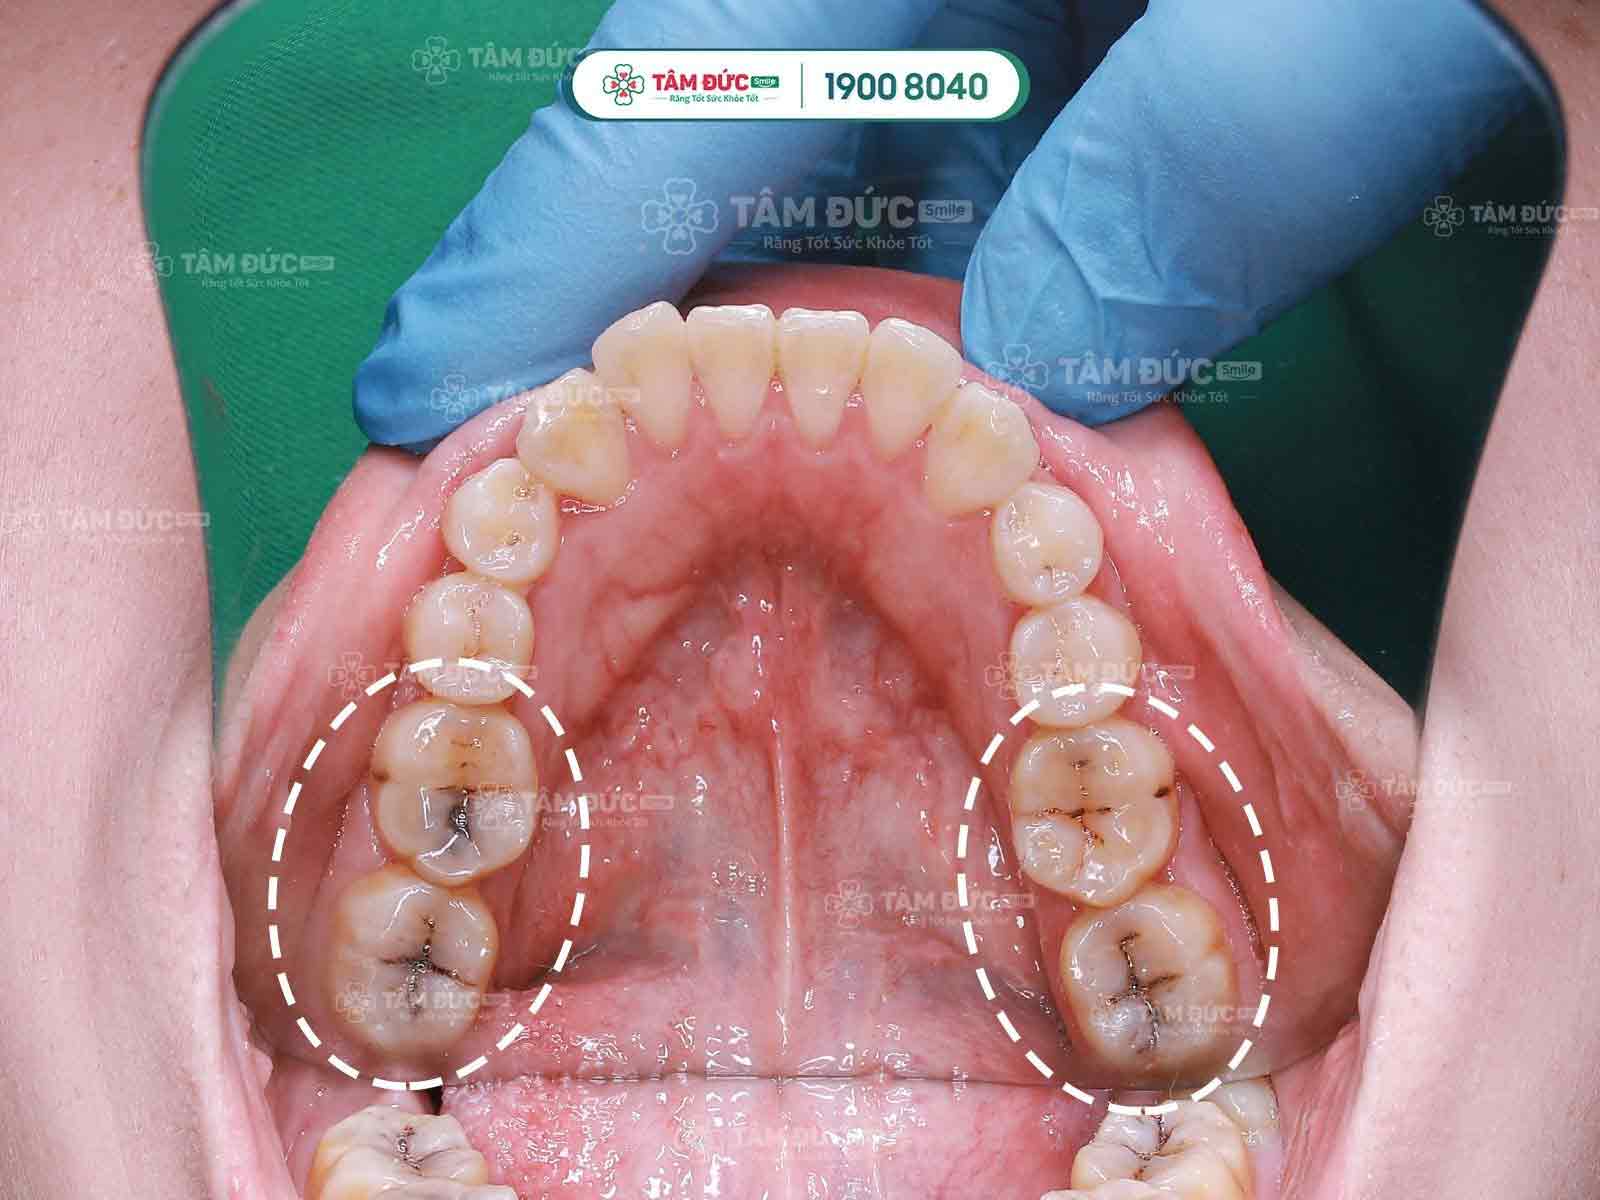

Khách hàng trám răng thẩm mỹ tại nha khoa Tâm Đức Smile

Mỗi một nụ cười hài lòng của bệnh nhân chính là thước đo giá trị chân thực nhất về chất lượng điều trị, dịch vụ tại Tâm Đức Smile. Đừng e ngại, hoặc chần chừ việc trám răng. Đặc biệt là răng sâu, viêm tủy… càng kéo dài thời gian càng khó bảo tồn răng thật sau này.